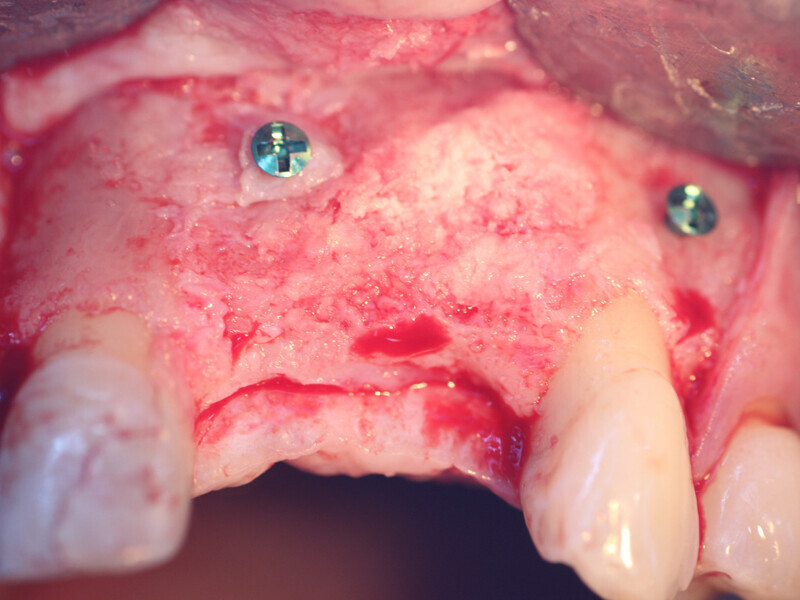

Fig. 10: Holes are placed through the Flexo-Plate Plus and fixation screws are placed to stabilize it on both left and right over the area being grafted.

Fig. 12: The PRP autogenous and particulate graft (‘gummy bone’) is placed into the space between the stabilized Flexo-Plate and the deficient edentulous ridge.